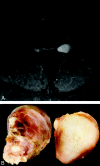

Histologic patterns of cellular architecture often suggest a tissue diagnosis. Distinctive histologic patterns seen within the peripheral nerve sheath tumor schwannoma include the Antoni A and Antoni B regions. The purpose of this report is to review the significance of Antoni regions in the context of schwannomas.